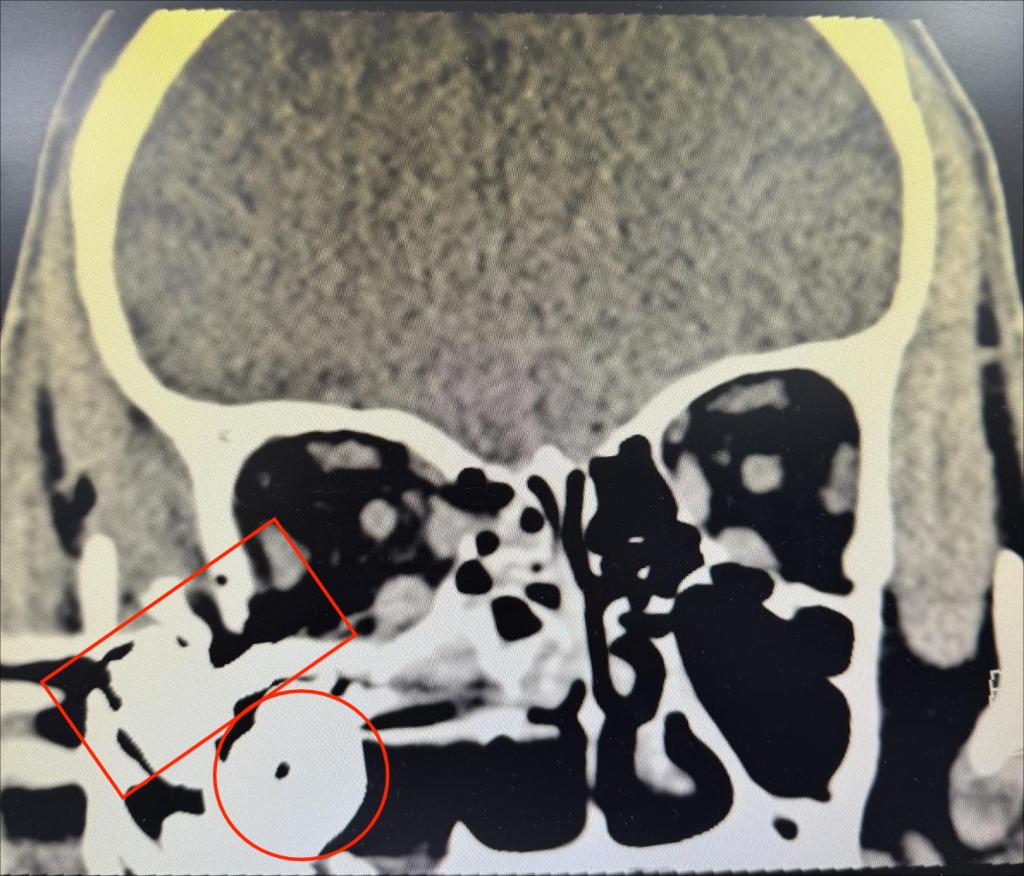

晚上九点多患者赶到医院,一直在病房等候的眼整形眼眶泪器病专业组长刘子瑶副教授、值班医生王艳芬、病房护士及手术室护士已经做好了各项准备,眼外伤急诊绿色通道畅通,1小时后患者已完成必要术前检查及准备,安然躺在了手术台上。经过仔细消毒冲洗探查伤口,主刀医生刘子瑶不禁捏了把汗,患者右眼睑皮肤全层破碎不堪,上下泪小管断裂,伤口深达眶骨,伤口内散在树枝、尘土等大量异物,面部皮肤满布黑色点状异物,眼球破裂,眼内容物大部分已流失,眼球结构已不成形。眼眶CT显示眶内及上颌窦内有巨大金属异物,但在探查过程中眼眶内无法探及异物。刘子瑶副教授像拼拼图一般,仔细辨认、对位破碎的眼睑结构,寻找到针尖大小的上下泪小管断端,精细缝合,经过3小时余的努力,成功吻合了泪小管,恢复了眼睑正常的外形,并清理了残余眼内容物,保留好巩膜、结膜结构,为二期安装义眼台做好准备。

眶内异物(图1)

眼眶CT显示异物位置(图2)

术后给予患者抗感染治疗的同时,刘子瑶副教授反复观察CT影像,考虑如此巨大的金属异物是如何进入眼眶和上颌窦的,又该如何在最小损伤的情况下将其取出呢。经与耳鼻喉科共同商议,异物取出手术定在5天后两科共同协作完成,耳鼻喉科由王波涛医生主刀,设计巧妙的口内唇龈沟切口,避免面部遗留手术痕迹,从上颌窦底部向上分离探查,终于顺利取出巨大圆柱形金属异物1枚,但与CT显示形状比对,应该还有另一块不规则形异物并突入眼眶内,继续由上颌窦底部向眶底探查,果然成功取出第二枚异物,这枚异物基底成圆柱形,底座上延伸出长约3厘米的突起,突入眶内。异物取尽后,刘子瑶医生为患者安装了义眼台,成形好结膜囊,静待恢复。时至现在,患者悬着的心终于落下,不再惊魂未定的他才愿意回忆并向医生讲述那天的爆炸伤,强大的冲击力使得巨大的金属异物打破眼睑、穿过眼球及眼眶,停在上颌窦内。目前患者已平稳出院,伤情恢复良好,眼部外观满意。